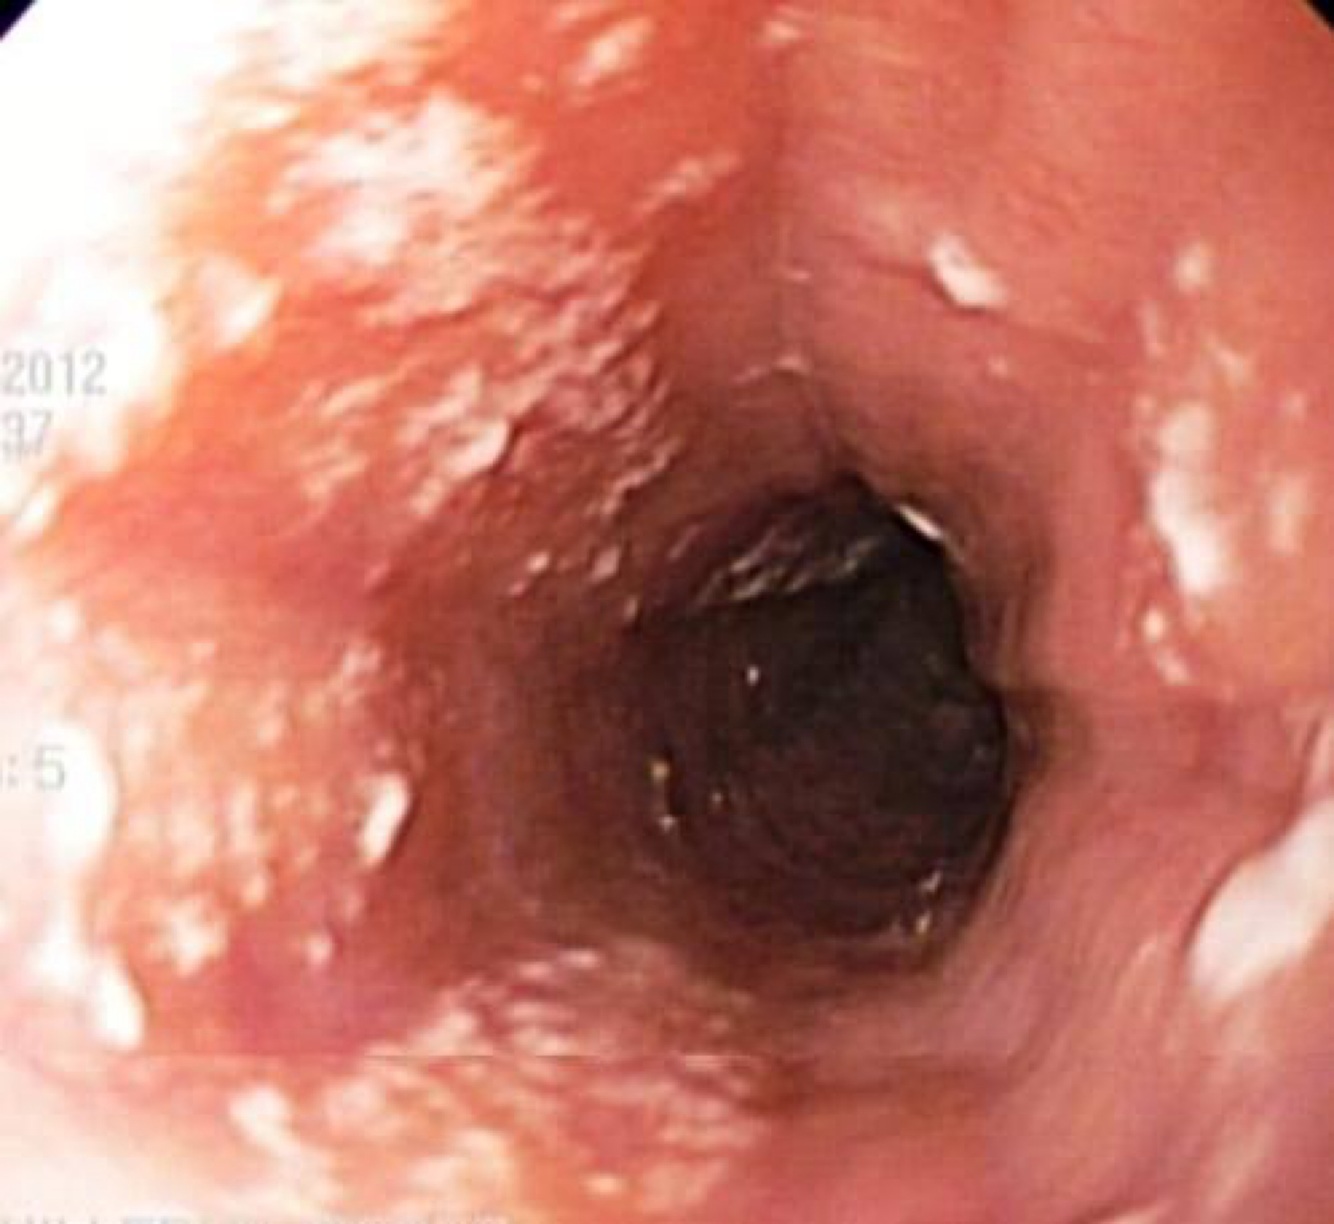

¿Qué caracteriza a la esofagitis candidiásica?

A

Dolor torácico, dolor al tragar, placas blanquecinas en la mucosa; definitoria de SIDA.